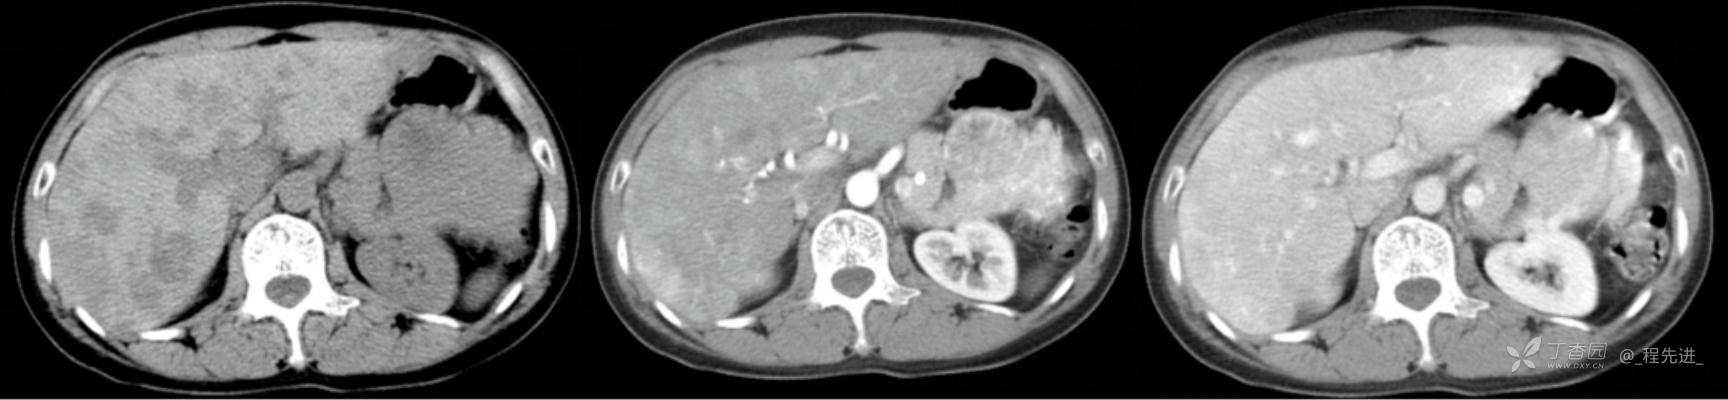

图像左边为平扫,中间的是动脉期,右边的是静脉期